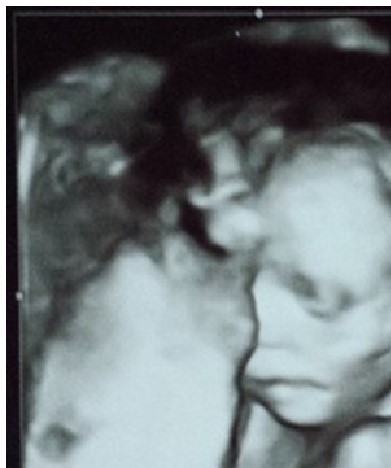

It’s common for prenatal care providers to offer ultrasounds at this point in pregnancy, so we have an abundance of images this week. Here are just a few. Thank you to everyone who donated!

The 20-week ultrasound is a wonderful opportunity for family members to bond with the baby, and it is often when the baby’s sex is revealed. Unfortunately, there is a darker side; this is also when parents may learn that their child has a disability, such as Down Syndrome, that is often accompanied by tremendous pressure from “pro-choice” medical professionals to abort. Hope Story is an excellent resource for families facing a prenatal diagnosis, where they can cut past the scaremongering and hear directly from other parents.